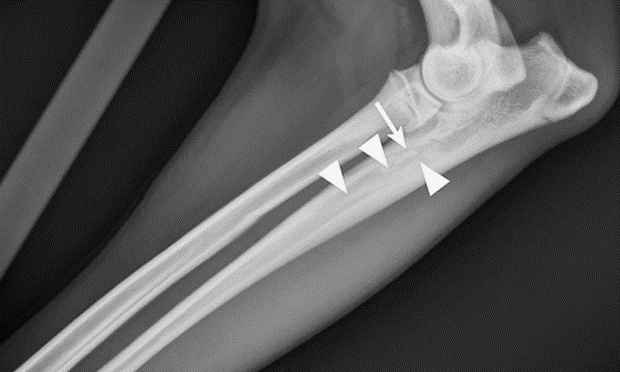

Určenie ochorenia prebieha na základe príznakov. Diagnózu potvrdzuje röntgen. V začiatku ochorenia sa vyskytuje nepatrné zvýšenie kostnej hustoty v strednej časti postihnutej kosti. V strednej fáze sa vnútro kosti stáva škvrnité, povrch kosti je drsný. V poslednej fáze je síce kosť stále škvrnitá, no pomaly sa vracia späť k normálu. .